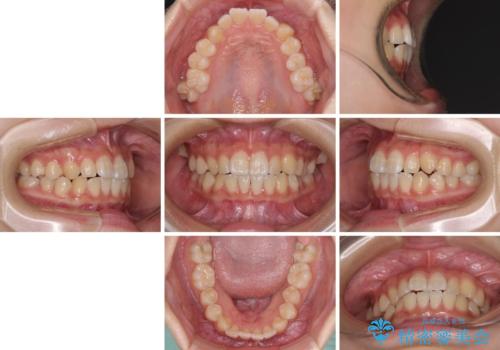

- 前歯のデコボコと磨きにくい奥歯を気にして来院された患者様です。

左右ともに上顎第二大臼歯が外側に転位しており、大変磨きにくくなっているため、補助装置により内側に引き込むことで改善することとしました。

外側を向いていた奥歯は比較的早い時期に歯列に収まり、咬み合わせも磨きやすさも改善することができました。

歯列は元々悪くなかったので、1年ほどで治療を終えることができました。